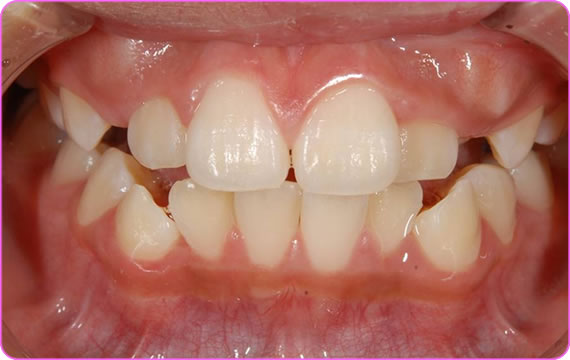

初診時

床矯正装置を装着

症例201604-8-1 床矯正

■年齢  6才

■性別  女性

■主訴

上下の前歯の不正

■問題点

上下のアゴが小さい

舌癖がある

舌が口を閉じても見えている状態